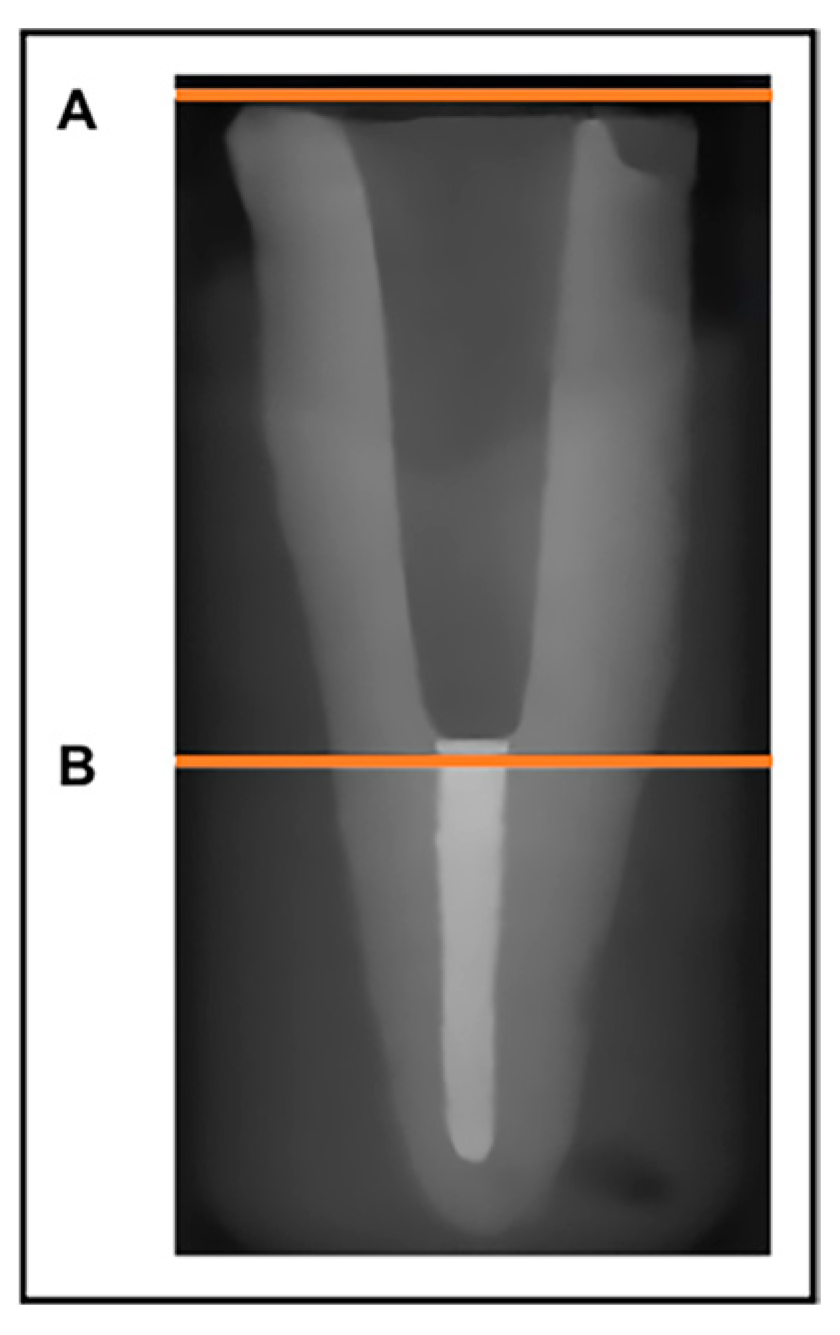

1. Introduction

2.3. Evaluation of Accuracy of Fit of Cast and Milled Post Cores

2.3.4. Measurement of Apical Gap Volume

2.3.5. Length of Apical Gap between Post and Remaining Gutta-Percha Root Filling

2.3.6. Measurement of Space between the Posts and Lateral Walls of Root Canal